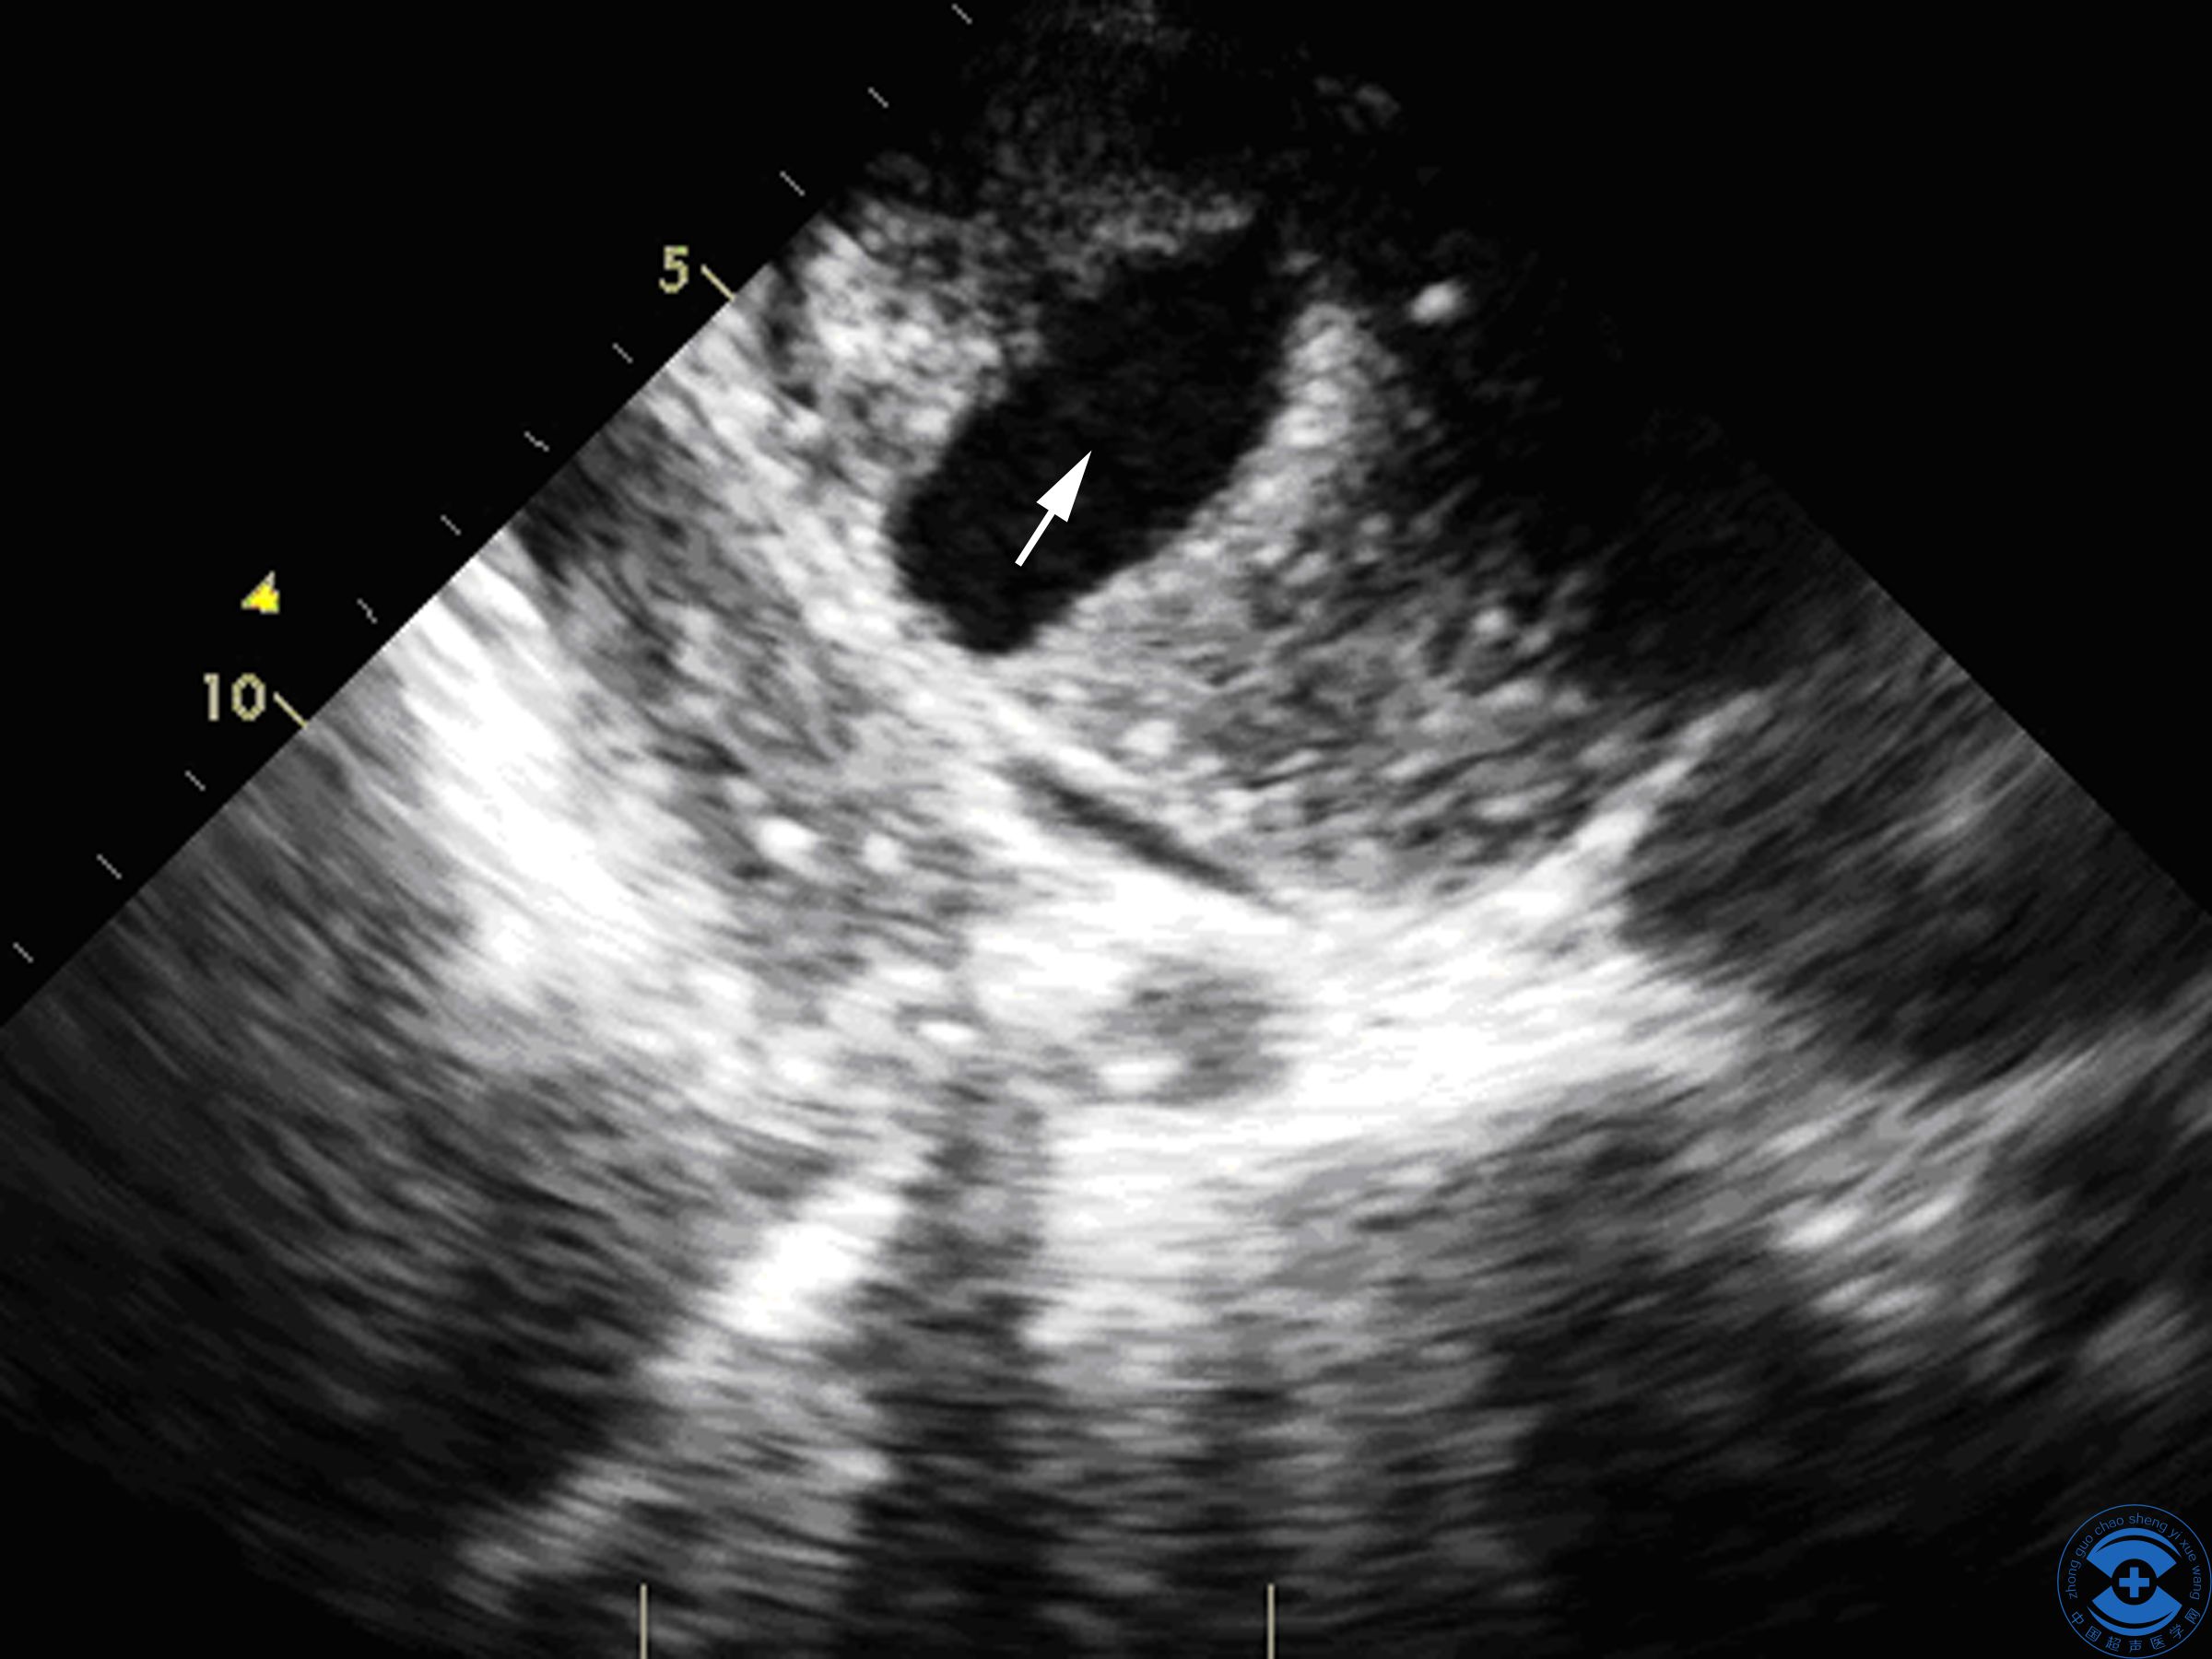

图2 室间隔内裂隙:探头由心尖两腔心切面向下扫查,箭头所示为左室下壁带状非贯通性

图3室间隔内裂隙:探头由心尖两腔心切面向下倾斜,箭头所示为带状非贯通性撕裂伤